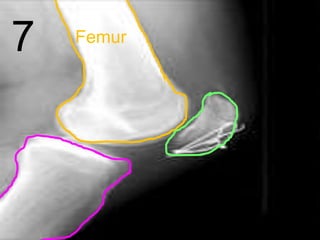

7

8